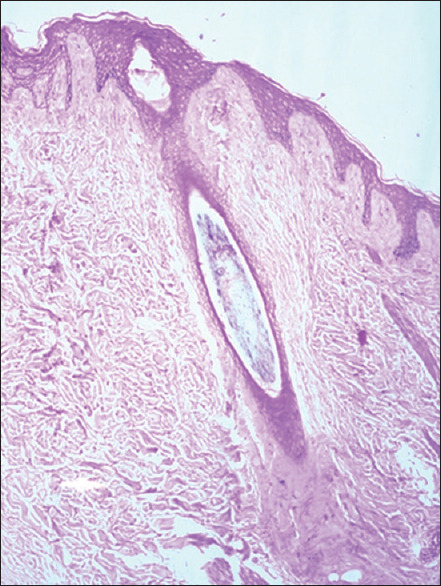

Materials and methods: This cross-sectional study was conducted over a period of 1 year in the department of dermatology and pathology in a tertiary care hospital in North India. Adult patients (age >18 years) presenting with patchy cicatricial alopecia as well as clinically doubtful noncicatricial conditions over the scalp were included in this study. In doubtful cases of noncicatricial alopecia, a single 4-mm punch biopsy was performed for transverse sectioning with hematoxylin and eosin stain. In all cases of cicatricial alopecia, two 4-mm punch biopsies were performed, one for transverse sectioning and the second for vertical sectioning and direct immunofluorescence (DIF). The final diagnosis was made on the basis of the trichopathologic findings.

Results: A total of 23 cases were included in our study with the majority (52.2%) being in the age group of 20-30 years. The mean age at diagnosis was 30.5 ± 11.38 years. On the basis of trichopathologic findings, a final diagnosis was made in 18 (78.3%) cases. However, 5 (21.7%) cases remained undiagnosed and were labeled as nonspecific. According to the final diagnosis based on the trichopathologic findings, maximum cases were of discoid lupus erythematosus (DLE) (26.1%), followed by lichen planopilaris (21.7%), pseudopelade of Brocq (13%), alopecia areata (8.7%), folliculitis decalvans (4.3%), and traction alopecia (4.3%). Trichopathologic examination revealed hyperkeratosis (60%), basal cell vacuolization (55%), epidermal atrophy (55%,) perifollicular lymphocytic infiltrate (30%), pigment incontinence (30%), perifollicular fibrosis (25%), and thickened basement membrane (25%). Only four cases showed deposits of immunoreactants in DIF and all four were finally diagnosed as DLE.